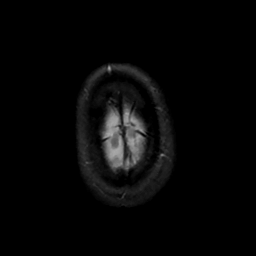

MR Study #12, May 12, 1991 -- Slice #47

[Home][Help][Clinical][Tour 1][Tour 2] Slice 47